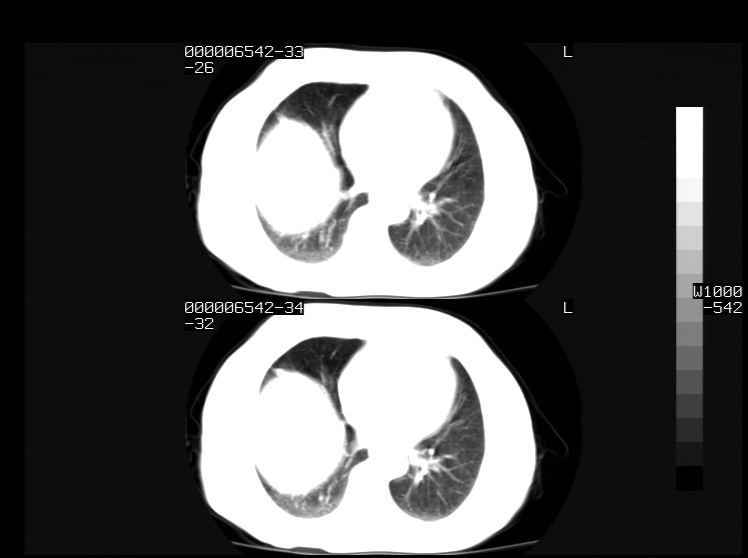

右侧膈膨升,胆囊壁厚,右侧肾脏缺如。病史?

右侧膈膨升,右肾脏切除术后

右侧膈膨升,肝内钙化灶,胆囊壁厚,右侧肾脏缺如。病史?

右膈膨出,肝脏变异,肝内钙化,右肾缺如,脾大。